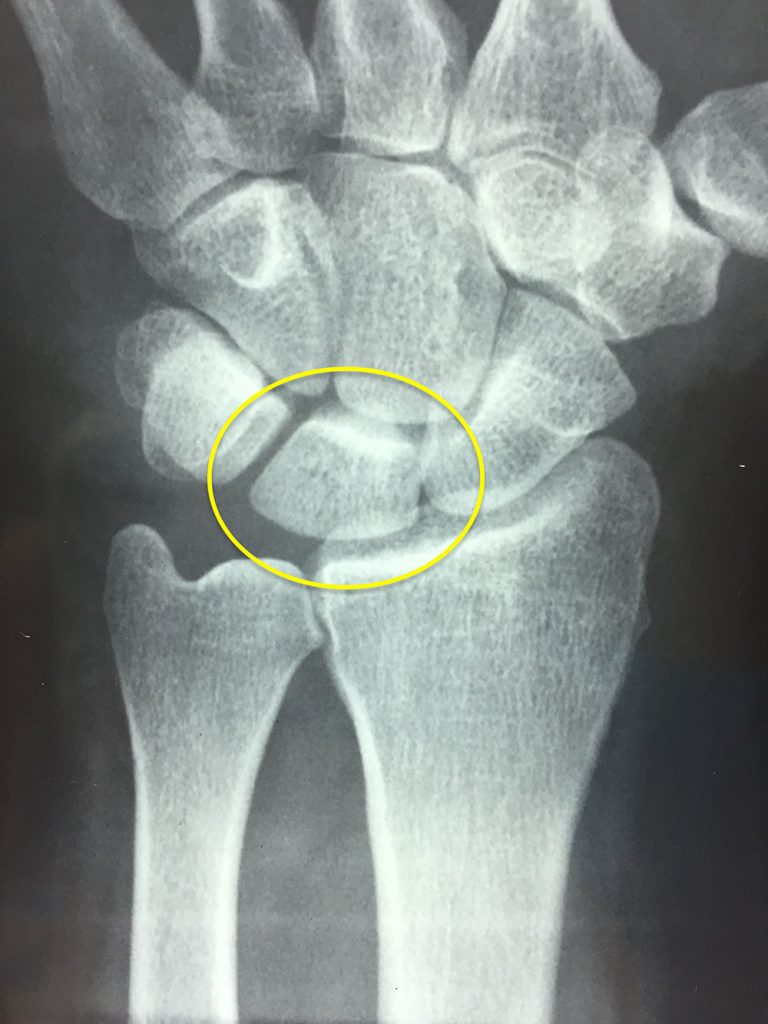

Las opciones de tratamiento dependen de la gravedad y el estadío de la enfermedad. En etapas muy tempranas, el tratamiento puede ser tan simple como la observación o la inmovilización. Para etapas más avanzadas (Figura 3), generalmente se considera el tratamiento quirúrgico, que dependerá de la situación específica de cada paciente. La fisioterapia no cambia el curso de la enfermedad, sin embargo, puede ayudar a minimizar el deterioro de la misma. El tratamiento está orientado a aliviar el dolor y recuperar la función.

Figura 3 - Colapso del hueso semilunar por enfermedad de Kienböck avanzada.